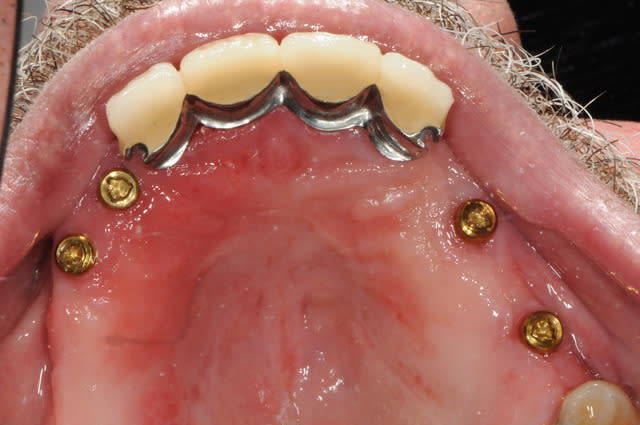

la suite c'est pose 4 implants, ceramique, stellite sur locators (beaucoup moins couteux qu'une barre et plus facile à nettoyer)

au final, c'est un patient heureux avec un stellite super stable.

Mais, juste à noter que sur le plan technique, 4 locators sur deux hemi-arcades : attention le parallélisme : trés trés délicat à gérer, au risque de se retrouver avec 3 actifs et un inutilisable.

ce que tu dis est parfaitement vrai pour des attachements boules (je les déconseille aussi fortement au maxillaire qu'on me les a déconseillé. car ce type d'attachement n'a pas de résilience et ne travaillent pas du tout de la même façon que des locators. les attachement boules ne peuvent pas rattraper les divergences d'axes que l'on obtient immanquablement au maxilaire au risque de "forcer" sur le métal.

seuls les locators ont une résilience suffisante pour encaisser le jeu qui existe.

pour moi (ce n'est que mon avis et j'en attends d'autres) cette résilience est la seule garantie d'avoir non pas 3 attachements actif et un passif mais 4 actifs "moyen"